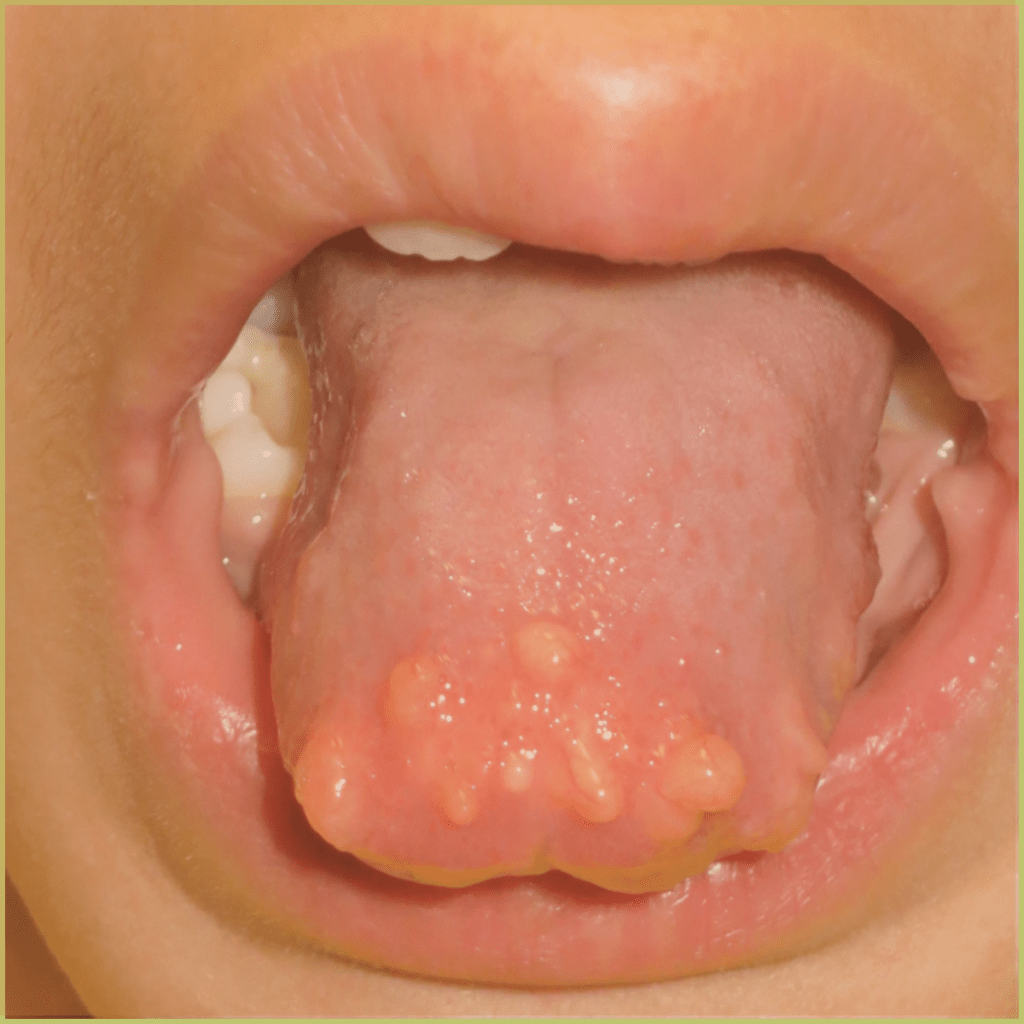

LINGUAL THYROID

Lingual Thyroid is a rare lesion in the oropharyngeal region caused by the failure of thyroid primordium to descend from the foramen cecum into the anterior neck. This results in thyroid tissue seen within the tongue. The exact mechanism is unclear. The common clinical presentation includes:

- Dark well vascularized mass on the midline of the tongue around the foramen cecum.

- May interfere with swallowing and breathing in infancy.

- Bleeding may occur.

Diagnosis is based on the lesion history, clinical presentation, and a positive radionuclide scan. Your differential diagnosis should include:

- Thyroglossal duct cyst.

- Squamous cell carcinoma.

- Lymphoma.

Treatment options include:

- Removal so long as it isn’t the only functioning thyroid tissue.

- Move/transplant lesion.